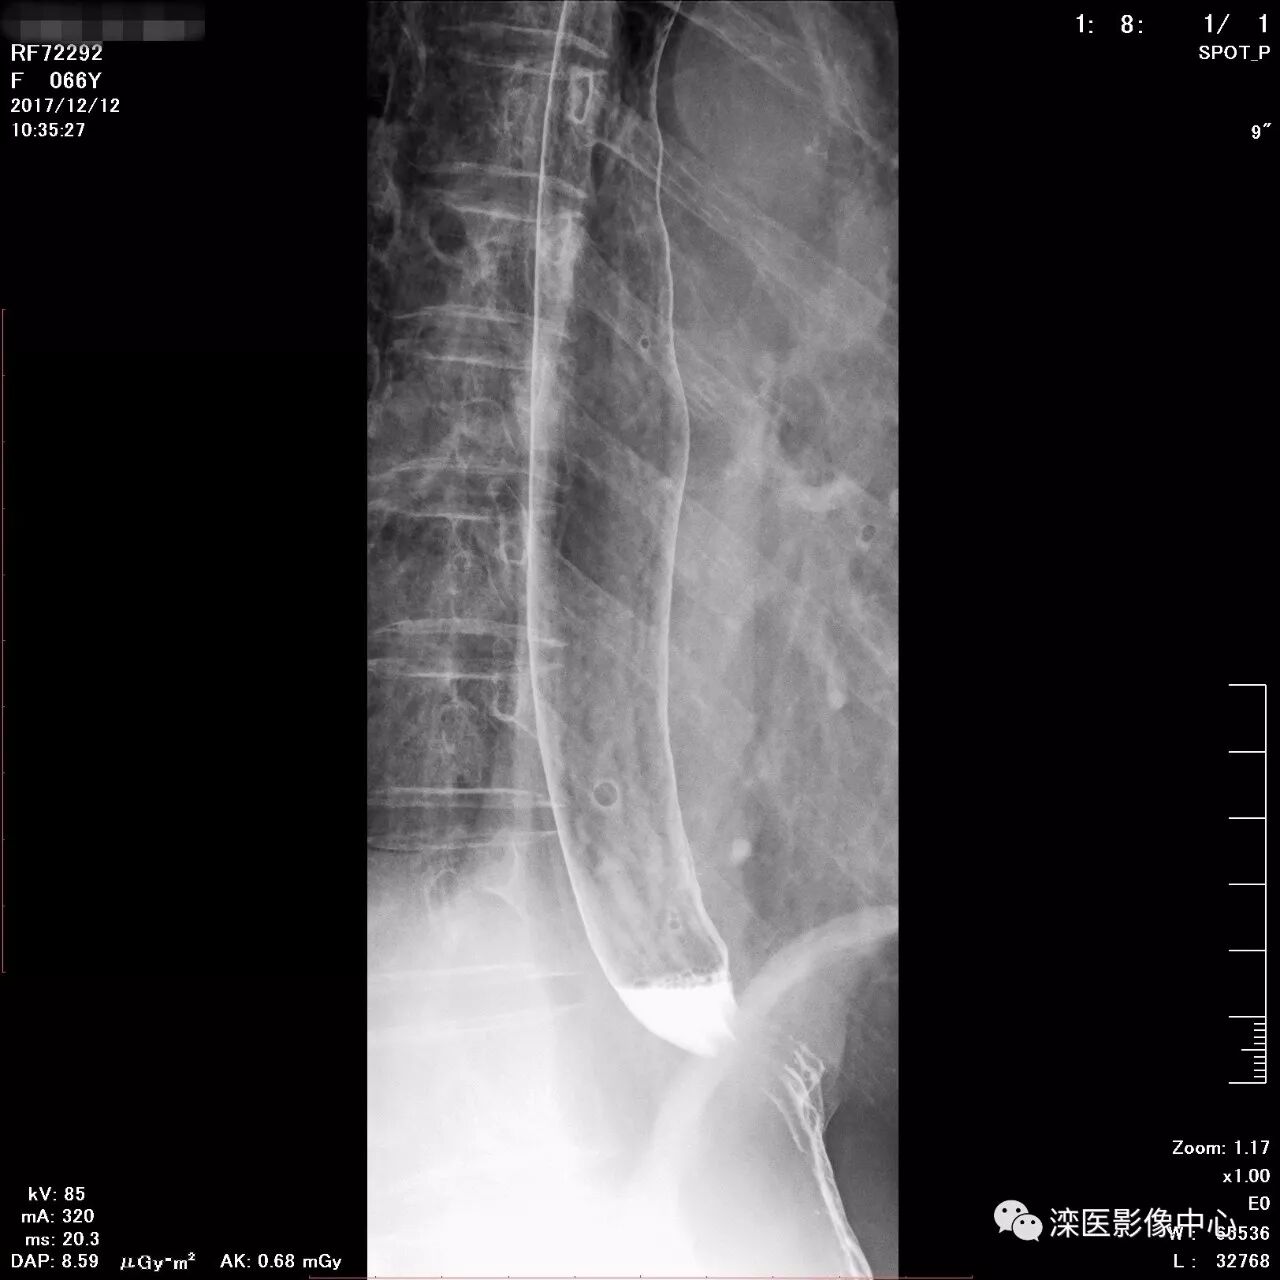

正位,显示食管、贲门及喉咽部的粘膜像)

(左前斜位,显示食管、贲门的粘膜像

(右前斜位,显示食管、贲门的粘膜像)

(以上图像是患者立位+卧位,通过变换体位,多角度显示了贲门胃底、胃体、胃大弯、胃小弯、胃窦、幽门及十二指肠球部、降部、水平部、升部的粘膜像和充盈像。本例患者女性,66岁,此次检查可以清晰显示胃小区结构,检查中发现患有慢性胃炎、胃下垂、十二指肠降部憩室)